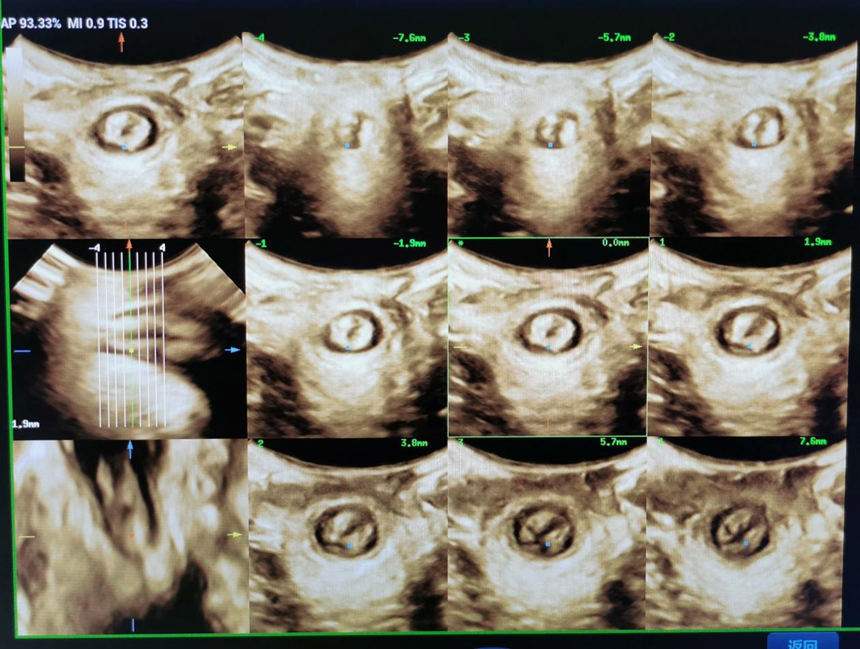

★ 在盆底肌收缩状态时,最重要的断层超声成像模式(TUI),此时层间距是2.5mm,层数为9层,即可获得多幅平行切面的肛提肌裂孔图像;标准要求第3-5幅图像所显示的耻骨联合必须分别呈现开放、闭合、闭合状态。肛提肌断裂时表现为基层回升不连续甚至完全不显示